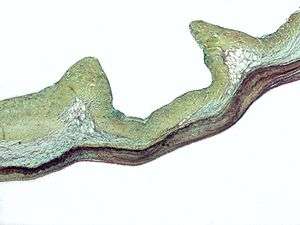

Micrograph of myxomatous degeneration – a cause of aortic insufficiency. | |